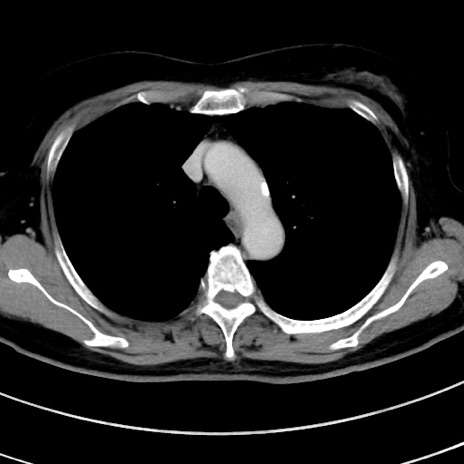

症例9(横断像)

【症例】 60歳代女性

【主訴】むかつき、みぞおちの痛み

【現病歴】3日前よりむかつきがあり、食事がとれない。

【既往歴】糖尿病

【身体所見】発熱なし、心窩部圧痛軽度あるも、腹膜刺激症状なし。

【データ】WBC 7400、CRP 1.92